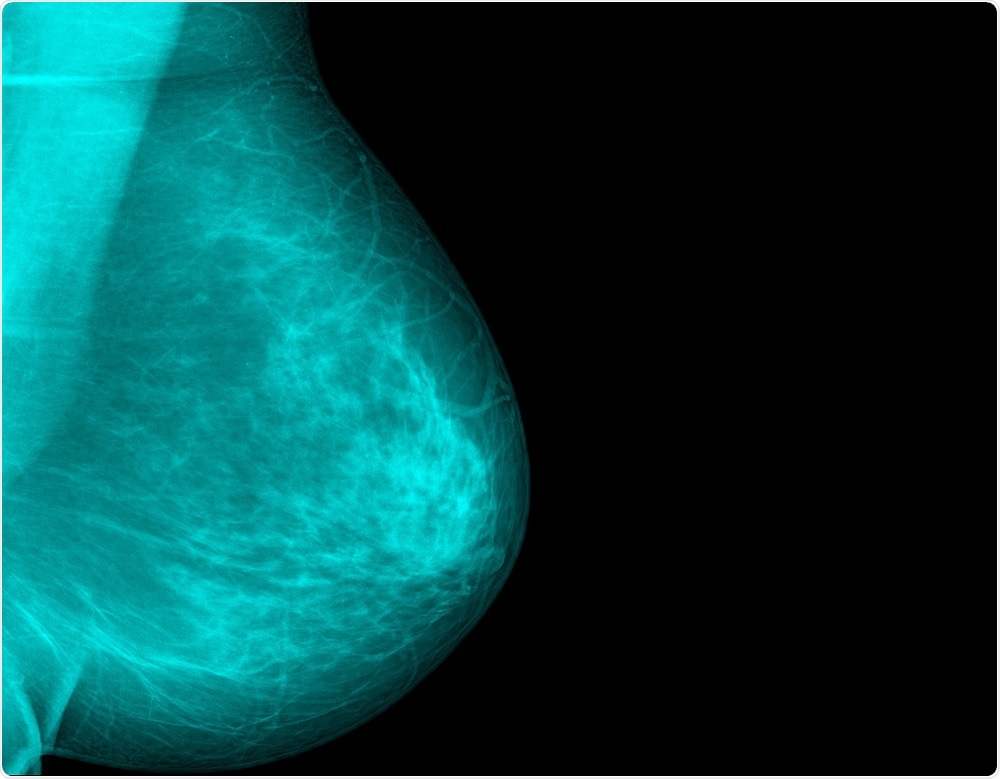

Breast density will be used to determine breast cancer risk, under the new regulationsXray Computer | Shutterstock

Dense breasts have more fibroglandular tissue relative to fat. This obscures the changes that arouse the suspicion of breast cancer, making the resulting images less sensitive and harder to interpret. To make things worse, dense breasts may be at higher risk for breast cancer.